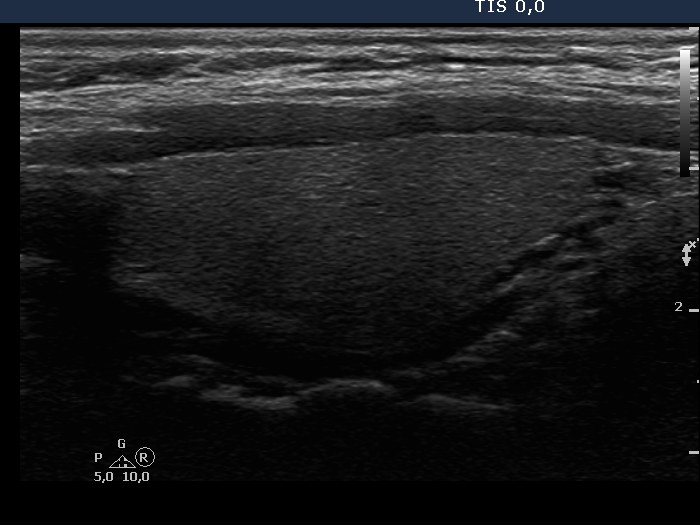

Chronic lymphocytic thyroiditis - Case 32. (ultrasonographic picture 2)

Right lobe, longitudinal scan.